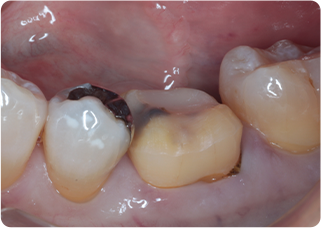

精密根管治療③

術前

術後

| 主訴 | 奥歯で噛むと痛い |

|---|---|

| 治療期間/回数 | 1ヵ月、4回 |

| 価格(税込) | 88,000円(税込) |

| リスク・副作用 | 病変再発、歯根破折の可能性 |

| ポイント | う蝕検知液を用い、むし歯の取り残しが無いようにし、ラバーダム防湿を行い、無菌的に根管治療を行った。根管充填材は、殺菌作用の強い保険適応外のMTAセメントを使用した。 |